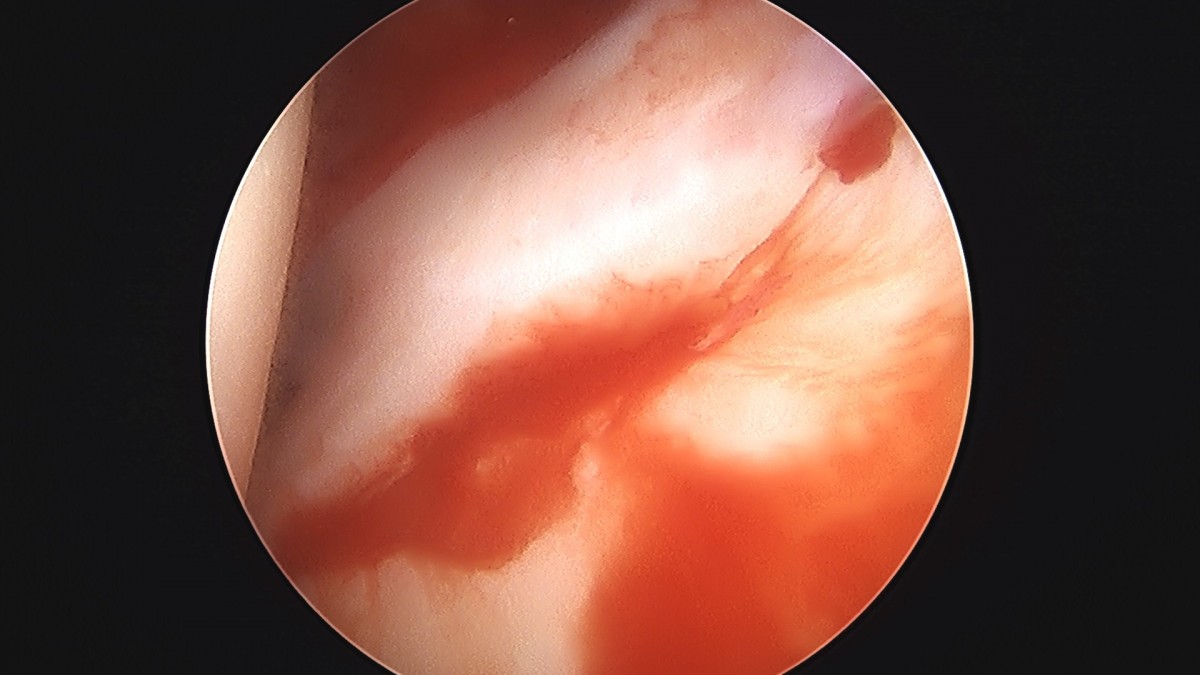

정지영원장님 어깨 관절낭 이완술 및 석회제거술 박설O 환자

작성자 최고관리자 댓글 0건 조회 732회 작성일 25-09-16 16:59